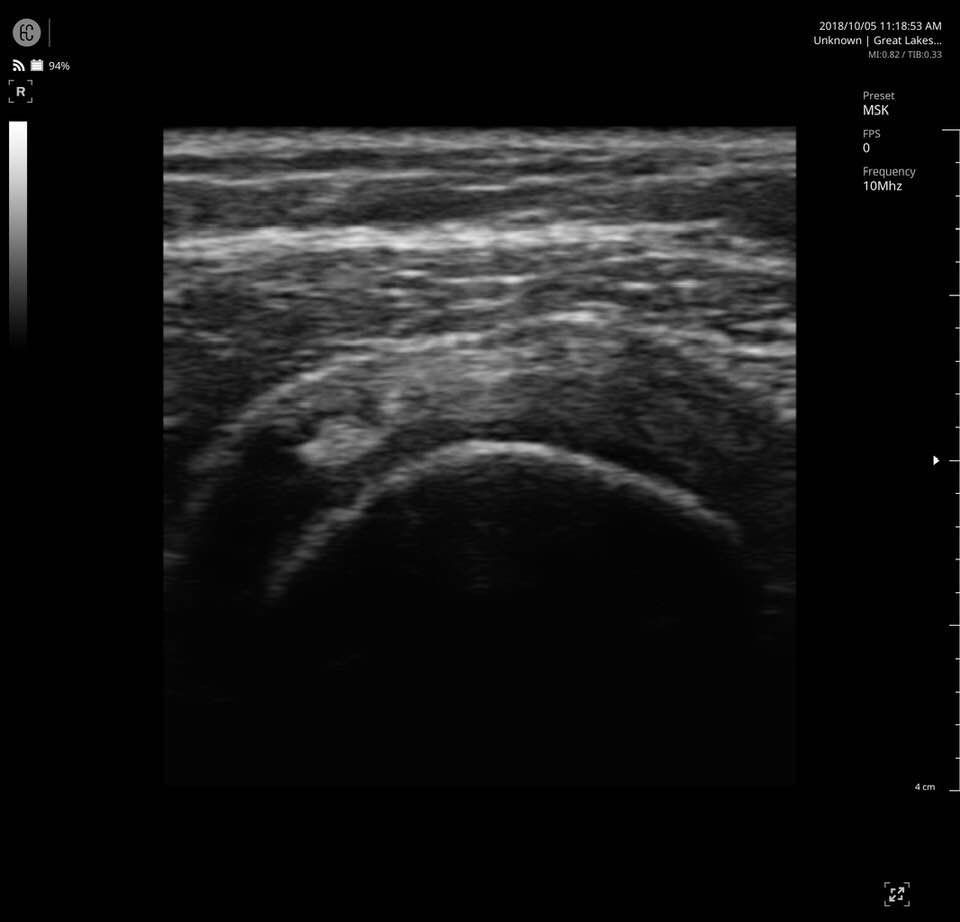

The SONON 300L transducer has cutting-edge technology and its software, combined with a proprietary sensor, turns any mobile device into a mobile ultrasound monitor with the same image quality and knobology as a traditional US machine. Software includes individual preset settings for your most common test.

- MSK

- Multi-frequency: 5MHz 7.5MHz 10MHz